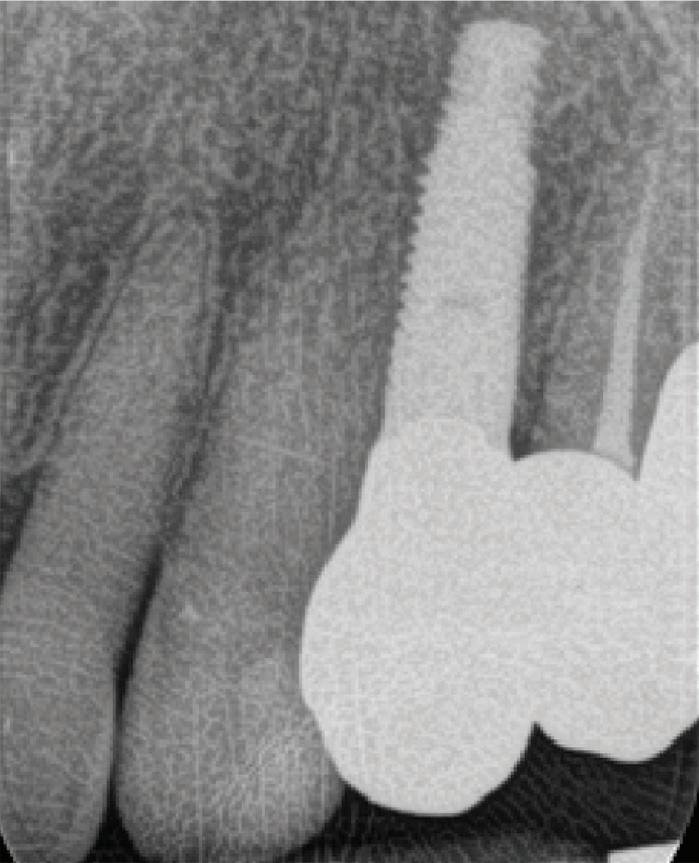

n Evaluating the digital workflow in implant dentistry: practical benefits versus technological novelty.

n Risk assessment (SAC), and the influence of implant type, material, surface characteristics and implant/abutment connections.

n Guidelines for implant planning, key parameters and management of peri-implant tissues.

n Immediate, early and late implant placement strategies.

n One-stage versus two-stage implant surgery techniques.

n Freehand versus guided implant placement methods.